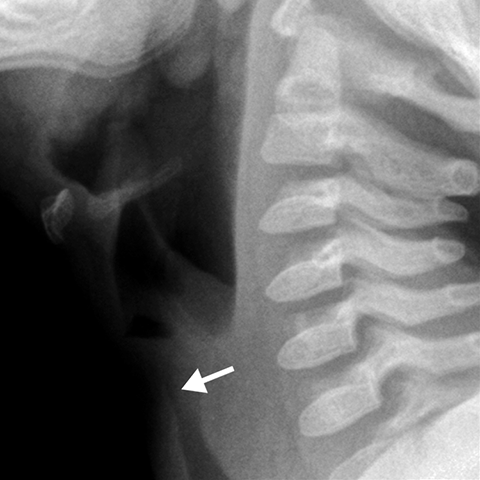

Croup [2 of 2]